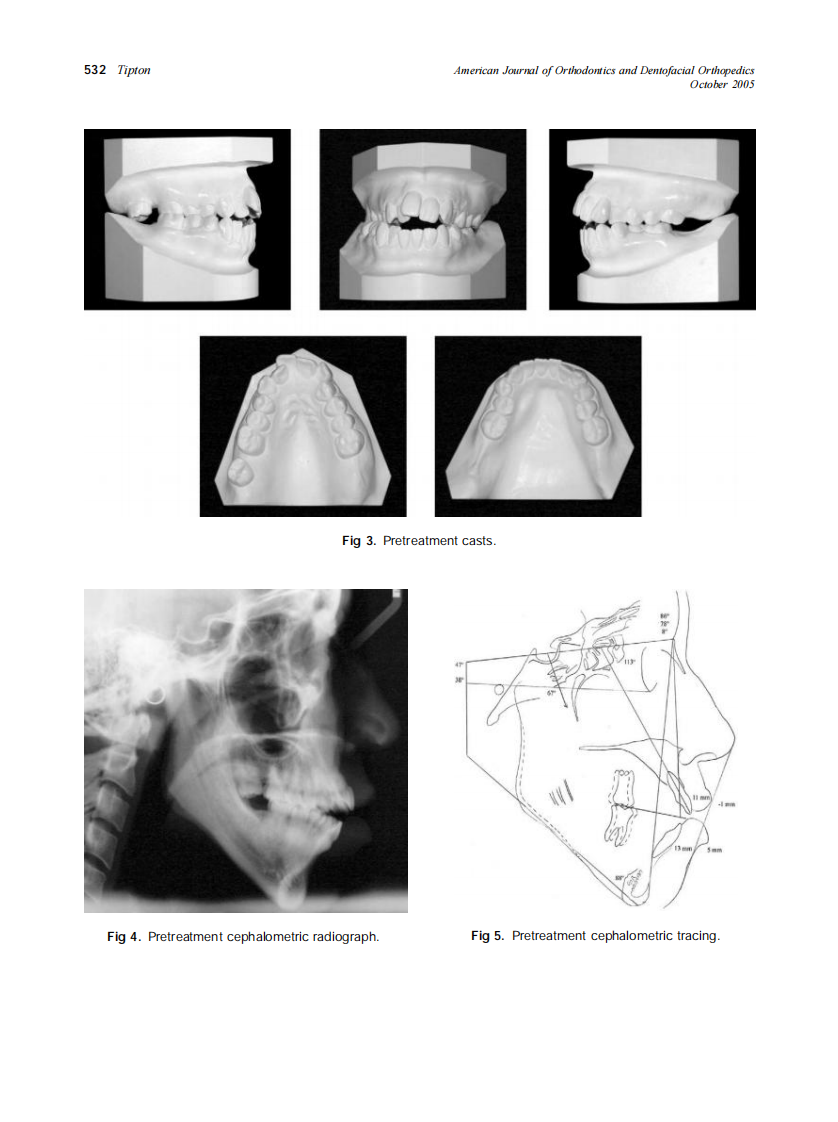

AJO-DO

2005_128_4_528_534_Tipton.pdf